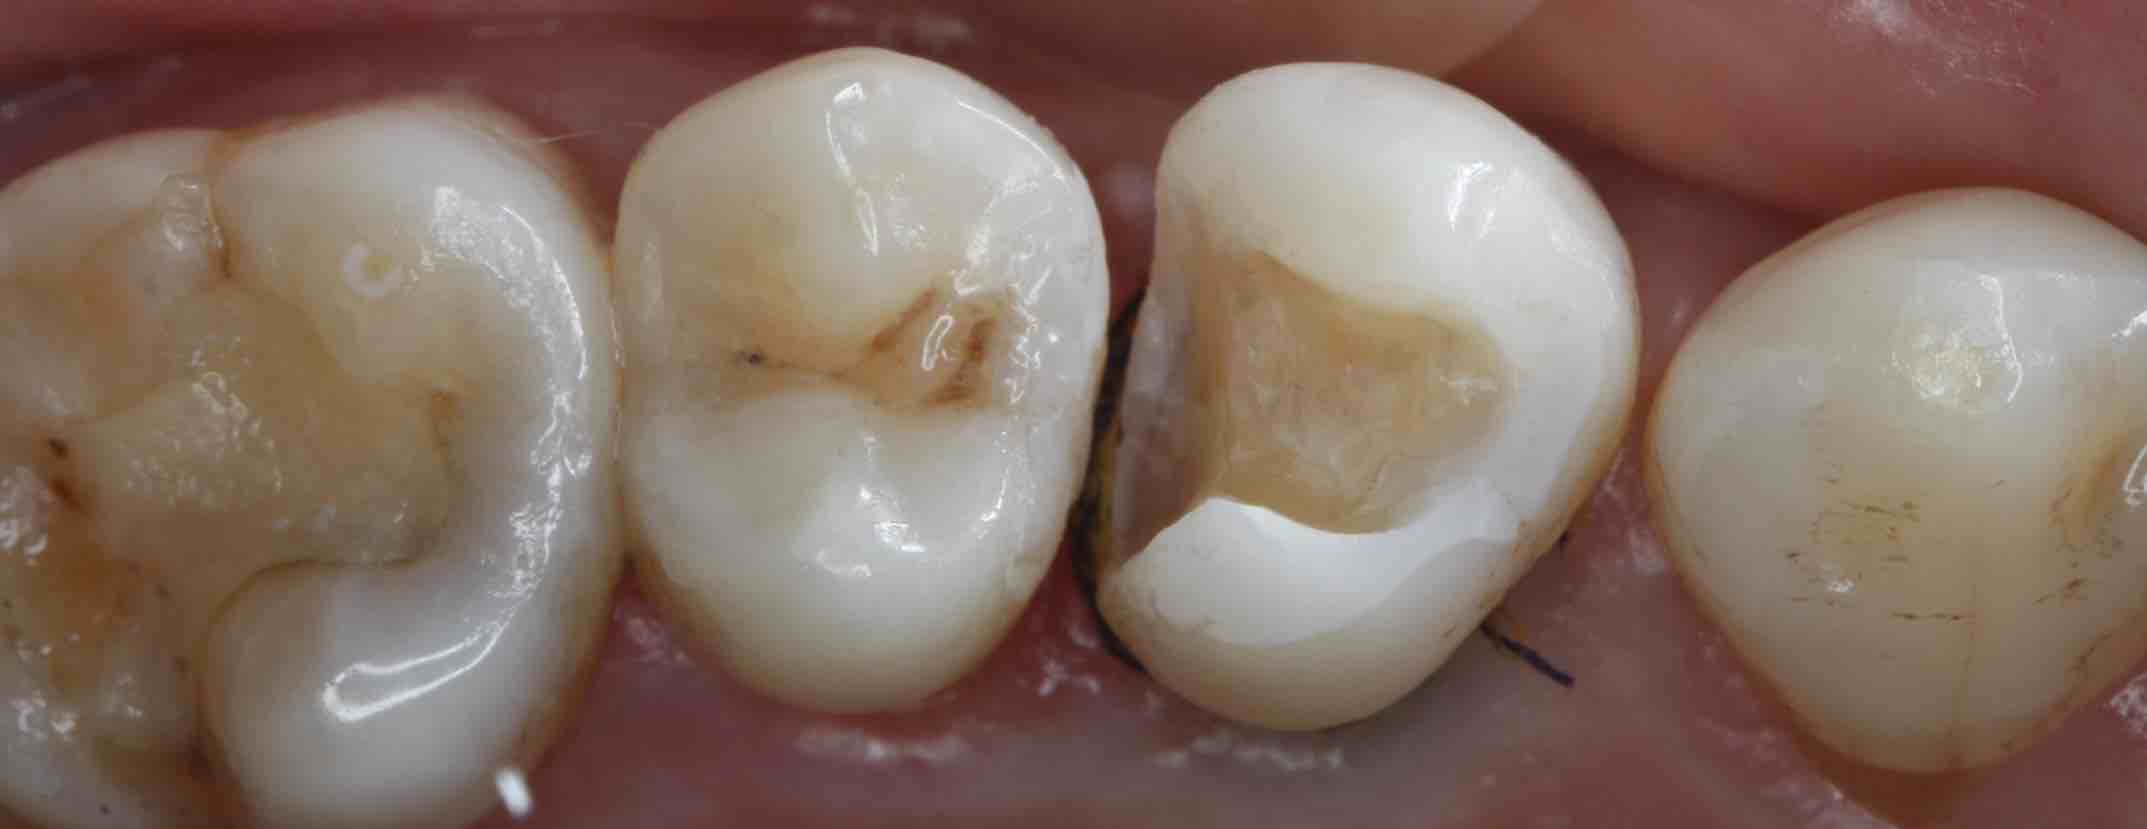

1. “不密合”是根源:银汞合金是金属,不会和牙齿产生化学粘结。时间长了,由于热胀冷缩或咀嚼力量,材料与牙齿之间会产生微小的缝隙。

2. “微渗漏”是通道:这条缝隙就成了细菌和食物残渣的“高速公路”,刷牙很难清洁到。细菌在此安家,久而久之,就从补牙材料的边缘开始,形成了新的蛀牙,这就是“继发性龋坏”。

当继发龋坏范围较大,或者原来的充填体已经不稳固时,简单的“重新补一下”可能不够牢固,容易再次脱落。这时,嵌体就是一个更优的选择。

· 高度密合:在口外精密制作,与牙齿的贴合度极高,有效封闭了边缘,从根本上减少了再次发生继发龋的风险。

· 坚固耐用:多采用高强度、美观的材料(如陶瓷、高强度树脂),耐磨耐用,使用寿命长。

· 恢复形态佳:能完美恢复牙齿原有的外形和咀嚼效率。